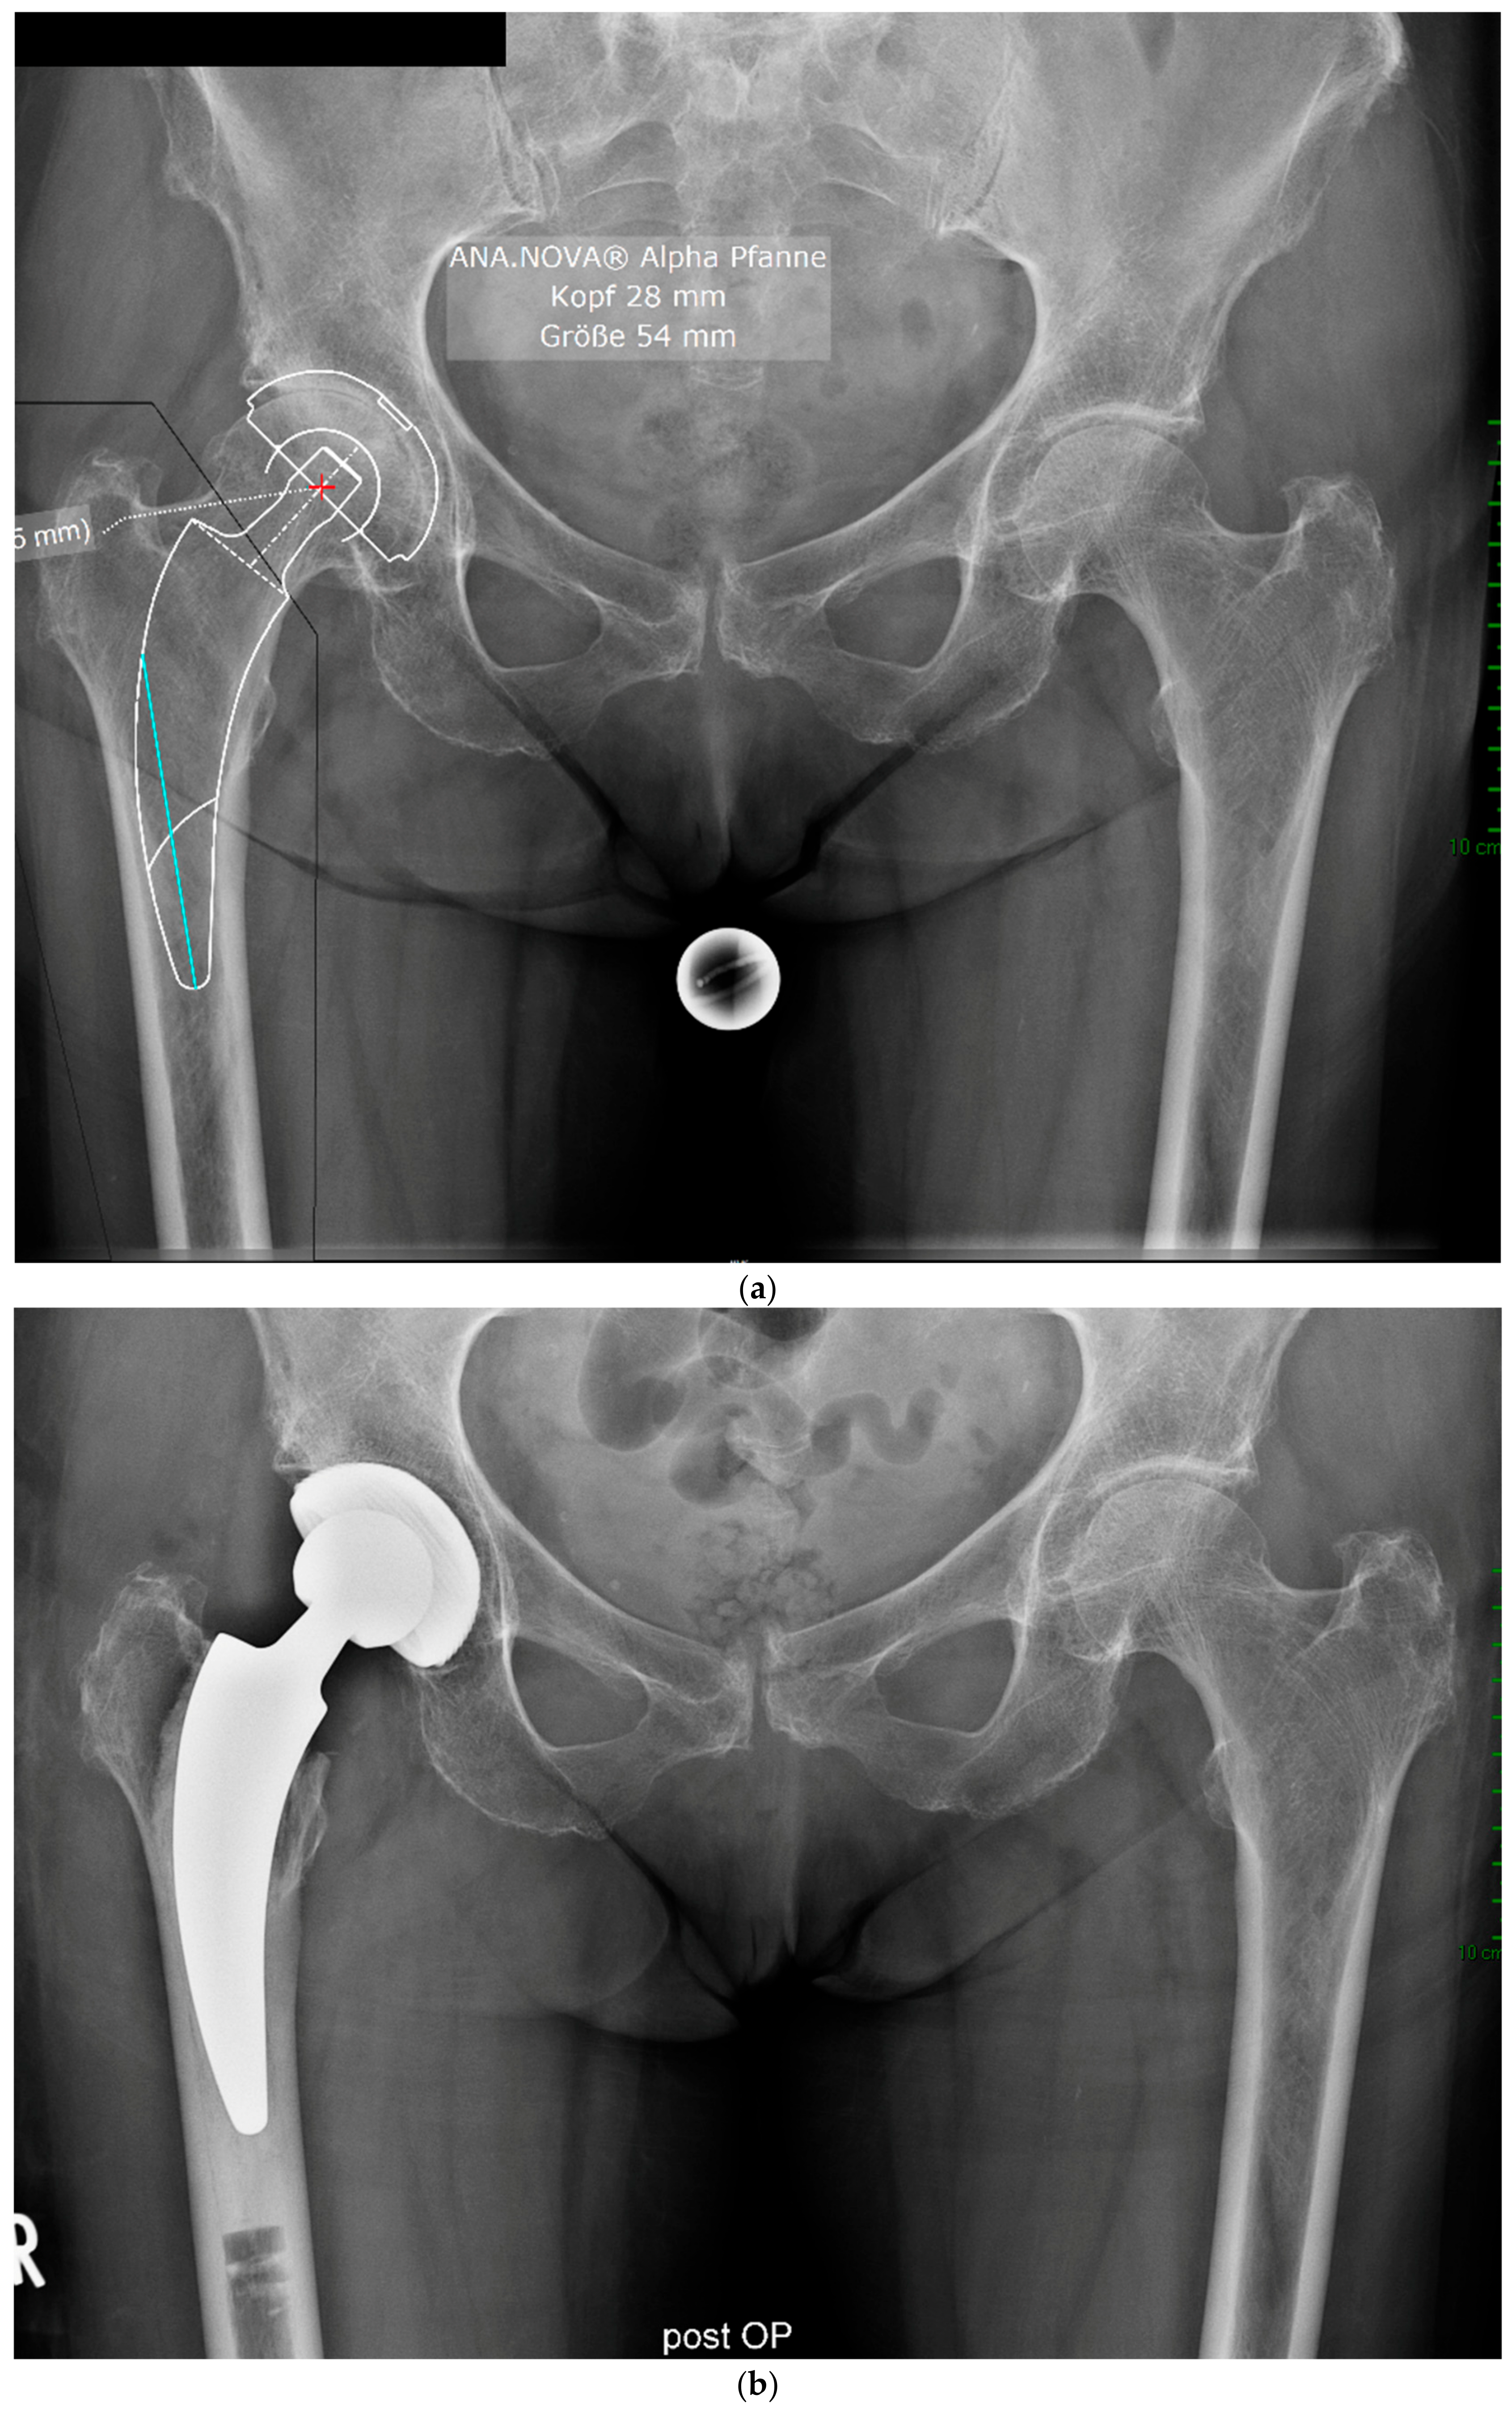

Figure 4.

(a) Case #3: Osteoarthritis, female, 81 years old, preoperative planning. (b) Correct implant position 1 week postoperatively. Homogeneous cement mantle.